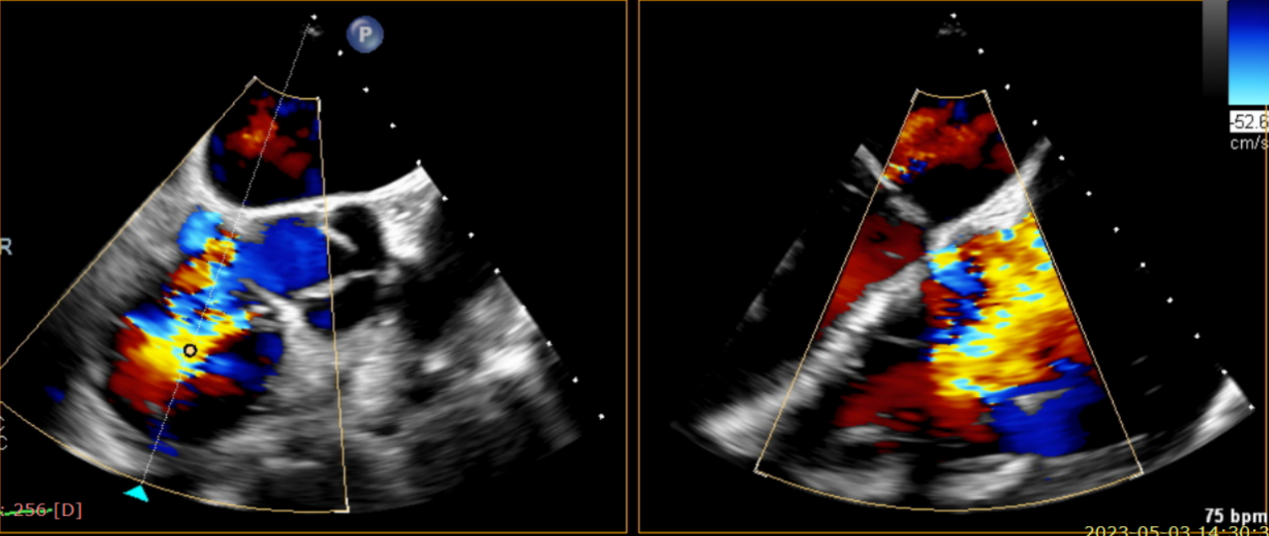

術(shù)前超聲提示大量三尖瓣反流

術(shù)中輸送器在超聲引導(dǎo)下調(diào)整位置

術(shù)后超聲提示僅殘余輕微瓣周漏